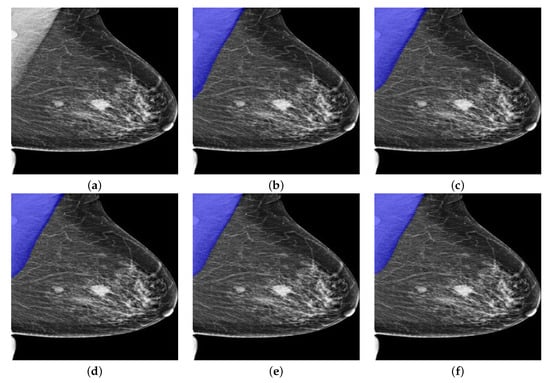

Similarly, we then performed our trained PeMNets to the same example image from INbreast for comparison. The results are shown in Figure 13.

As can be seen from Figure 13, all PeMNets presented successful segmentation results while P e I R v 2 provided best segmentation results with 99.91% of IoU, 99.96% of GPA, 99.14% of DSC, 98.30% of Jaccard, 99.96% of Sensitivity, and 99.95% for Specificity. Furthermore, it is worth noting that some PeMNets, such as P e R 50 , P e X c e p , also achieved comparable segmentation results while some of them even obtained 100% Sensitivity. From the above experiments, we can conclude that P e I R v 2 was the best model for pectoral muscle segmentation in terms of the evaluation metrics. However, P e M o v 2 turned out to be preferable considering the trade-off between the size of the model and the performance gained.

Figure 13. A segmentation example from INbreast by PeMNet with different backbones. (a) Pre-processed image. (b) P e R 18 : 99.27% of IoU, 99.93% of GPA, 98.40% of DSC, 96.85% of Jaccard, 100% of Sensitivity, and 99.86% of Specificity. (c) P e R 50 : 99.42% of IoU, 99.94% of GPA, 98.55% of DSC, 97.14% of Jaccard, 100% of Sensitivity, and 99.89% of Specificity. (d) P e M o v 2 : 99.46% of IoU, 99.84% of GPA, 98.67% of DSC, 97.37% of Jaccard, 99.75% of Sensitivity, and 99.92% of Specificity. (e) P e X c e p : 99.64% of IoU, 99.96% of GPA, 98.85% of DSC, 97.72% of Jaccard, 100.00% of Sensitivity, and 99.93% of Specificity. (f) P e I R v 2 : 99.91% of IoU, 99.96% of GPA, 99.14% of DSC, 98.30% of Jaccard, 99.96% of Sensitivity, and 99.95% of Specificity.